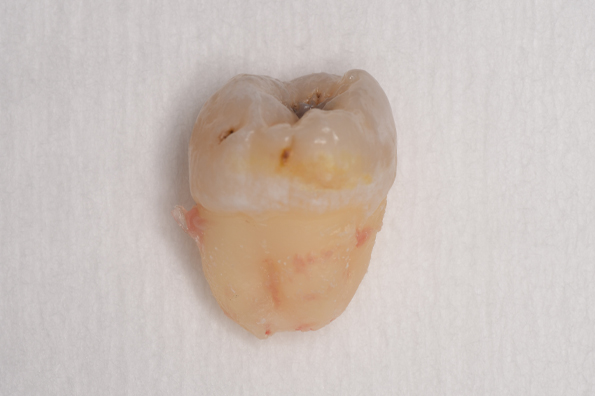

CASE 1

基本情報

| 年齢・性別 | 30代・女性 |

| 主訴 | 左右に分けて親知らずを抜きたい、できれば痛くなく抜きたい |

| 親知らずのはえ方 | 完全に出ていてまっすぐはえている |

| 抜歯期間 | 15分 |

| 抜歯費用 | 約2,000円(保険内) |

| 抜歯内容 |

何度か虫歯になり痛みはないが早めに抜きたい。 完全に頭が出ているため歯ぐきを切ったり骨を削らずに抜歯しました。 根の形も単純なため抜歯自体は5分もかからず上下ともに終わりました。 術後痛みや腫れも出ていません。 抜歯後は感染をしやすいため必ず抗生物質を飲み切ってください。 |